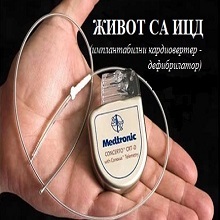

ИЦД је скраћеница за имплантабилни кардиовертер-дефибрилатор. Реч је о веома малој металној справи која се уграђује под кожу на грудима, а чије електроде се протежу до срца. ИЦД можда није ни видљив испод коже, али се може осетити. ИЦД може да осети откуцаје срца, може да препозна појаву малигне аритмије, а ако је открије, у стању је да одмах пошаље струјни удар у срце, који ће, у идеалном случају, „поново покренути“ срце и „бацити“ назад нормалан ритам. |